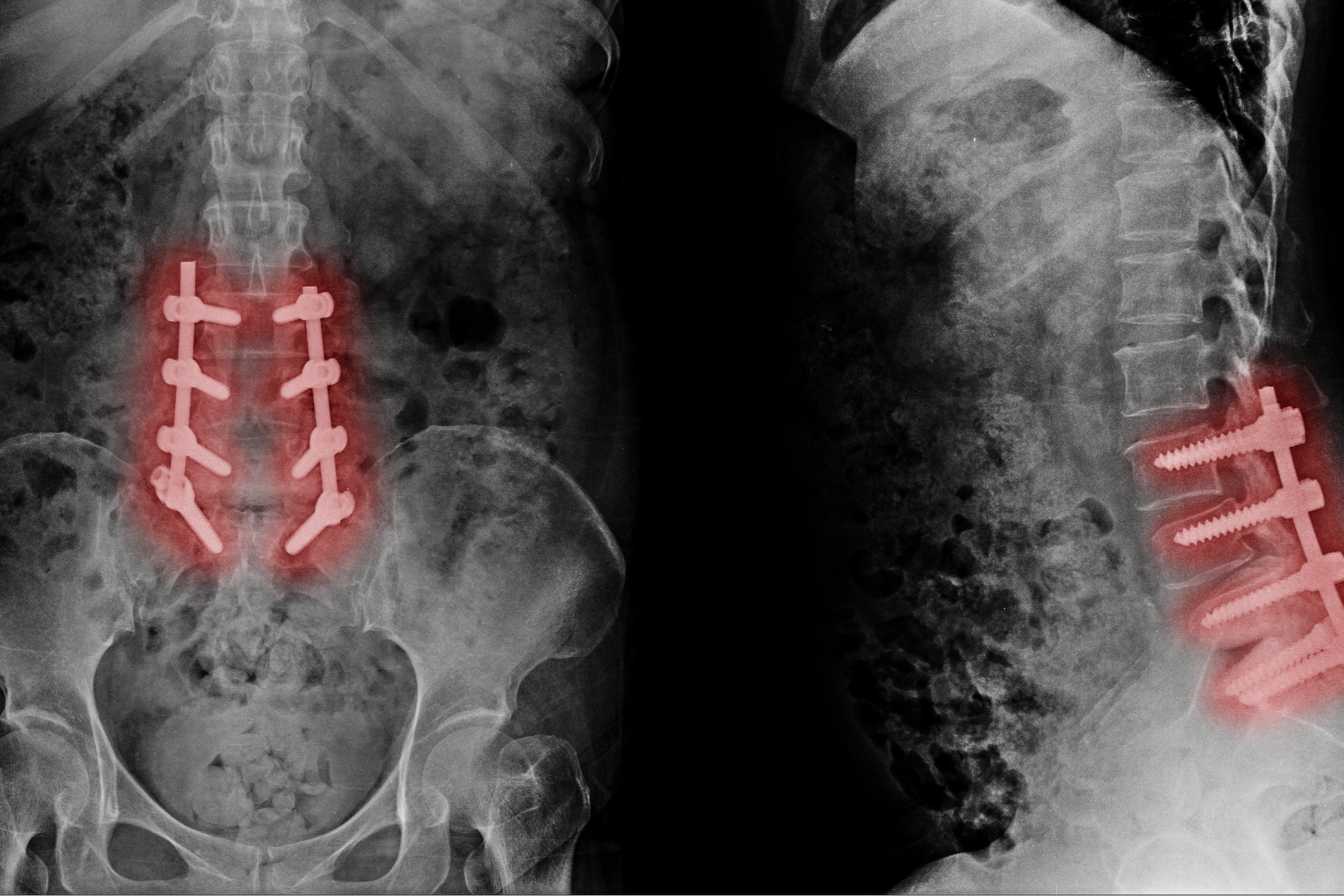

Peut-on travailler avec une discopathie dégénérative ?

Main illustration associated with the content.

La discopathie dégénérative correspond à l'usure progressive des disques intervertébraux, ces structures situées entre chaque vertèbre qui servent d'amortisseurs. Avec le temps, ils perdent en hydratation et en hauteur. Le rachis lombaire est le plus fréquemment touché, mais les cervicales peuvent l'être aussi.

Les symptômes varient selon les personnes. Certains ressentent des douleurs chroniques diffuses dans le bas du dos, d'autres subissent des crises aiguës avec irradiation dans la jambe — ce qu'on appelle une sciatique ou une cruralgie. Les raideurs matinales, la fatigue posturale et la difficulté à rester longtemps dans la même position font partie du quotidien de nombreux patients.

Ces limitations ont un impact direct sur la capacité à travailler, selon que votre poste exige de soulever des charges, de rester debout ou de rester assis des heures sans bouger.